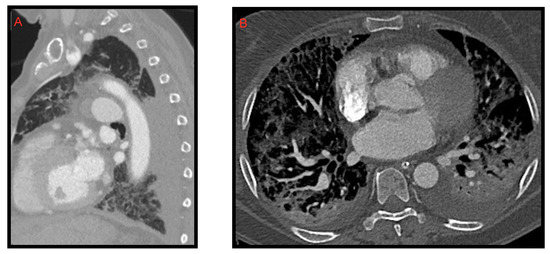

Figure 3. A 58-year-old female patient with worsening respiratory function on the 10th day of hospitalization evaluated with CT. Sagittal (A) and axial (B) images show posterior pleural effusion greater on the left side.

Figure 4. Pericardial effusion on CT, sagittal (A) and axial (B) images, in two patients admitted to intensive care unit. In image B, bilateral pleural effusion is also noted.

2.2. Pleural Effusion

Pleural effusion is rarely associated with COVID-19. We often find it in the most critically ill patients and in the most advanced stages of the disease (Figure 3). Zhou [11] et al. described pleural effusion in 3.2% of COVID-19 patients while Grassi et al. [9] observed it in 14.3% of cases. Darwish et al. [12] found that during the first week of infection pleural effusion occurs only in 13.6% of patients. Xiao li et al. [10], in regard to pleural effusion, reported a frequency of 14.3% and concluded that it was not significantly associated with COVID-19 pneumonia.

2.3. Pericardial Effusion

Pericardial effusion can be defined as the presence of more than 50 mL of liquid between the pericardial sheets. As already mentioned for the pleural effusion it is not characteristic of the COVID-19 thoracic involvement. In fact, it was observed by Li et al. [8] in 4.8% of cases. However, in this study, it is also described as a manifestation associated with the most compromised patients (Figure 4).

Ali Sabri et al. [13] found a 7.9% frequency of pericardial effusion. Furthermore, from their analysis, it emerged that pericardial effusion could be considered an important factor for admission to intensive care unit (ICU), as it could be an indicator of myocarditis or cardiomyopathy caused by COVID-19, but they did not confirm this hypothesis with echocardiography.

Grassi et al. [9] describe pericardial effusion in 16.7% of patients, proposing a relation with heart damage; Shi et al. [14] associated it with a higher risk of in-hospital mortality.